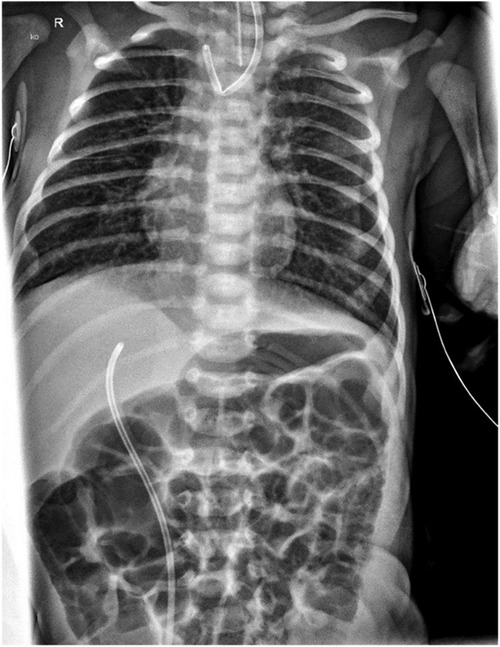

A thoracic radiograph demonstrated characteristic findings of EA and distal TEF with gas in the abdomen (Figure 1). Further clinical evaluation, including sonography and echocardiography, excluded associated congenital anomalies. Subsequently, thoracoscopic ligation of the fistula with primary anastomosis was scheduled for the second day of life.

Figure 1. Preoperative thoracic x-ray: proximally flipped Replogl tube and normal abdominal gas distribution, indicating TEF.